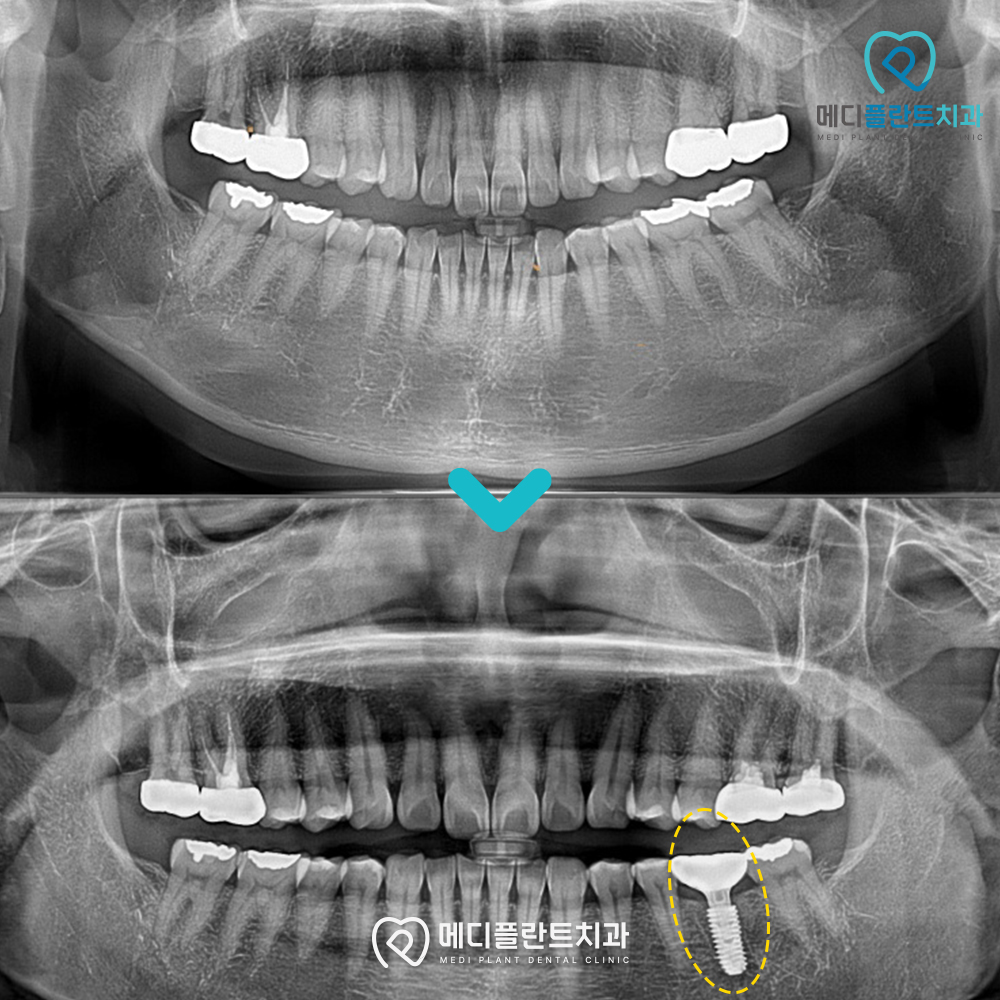

환자분은 어금니 부위의 불편함과 함께

기존 보철물 주변으로

이물감과 간헐적인 통증을 느껴 내원하셨습니다.

방사선 검사 결과

기존 치료 부위 아래쪽으로

골소실이 의심되는 모습이 관찰되었으며,

.

염증 가능성 또한 염두에 두고

추가적인 확인이 필요한 상태였습니다.

이처럼 겉으로는 큰 이상이 없어 보여도

내부에서는 변화가 진행되는 경우가 있기 때문에

정밀한 확인 과정이 중요한데요.

기존 보철물의 상태와

주변 조직의 변화를 함께 고려하여

현재 상태에 맞는 임플란트 치료를

단계적으로 진행하였습니다.